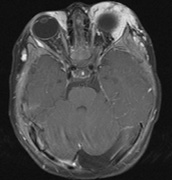

1. Schwannomas most commonly affect the fifth cranial nerve (CN), but any cranial nerve may be affected. In contrast to vestibular schwannomas (CN VIII), these typically do not grow large.84,90 Vestibular schwannomas (acoustic neuromas) are the classic finding in NF2 (Fig. 7). The risk for malignant transformation is low, but may be higher with radiation exposure.84,94

Fig. 7. Neurofibromatosis type 2: Images of a 12-year-old boy with deafness and weakness in his arms and legs, whose father has bilateral deafness. Axial T2-weighted (a) and postcontrast axial (b) T2-weighted images reveal bilateral vestibular schwannomas, which are also known as acoustic neuromas (arrows). This is the classic finding of NF2. (b, c) Bilateral schwannomas are seen in Meckel's cave (arrowheads) and a (d) lower left cranial nerve schwannoma extends into the pars nervosa of the jugular foramen (arrow). (e) A part cystic and part solid enhancing ependymoma in seen within the cervical cord and medulla and within the distal cord and conus. (e, f) Thoracic schwannomas are present at numerous levels (arrowheads). Marked enhancement and thickening of the roots within the cauda equina also represent multiple schwannomas.